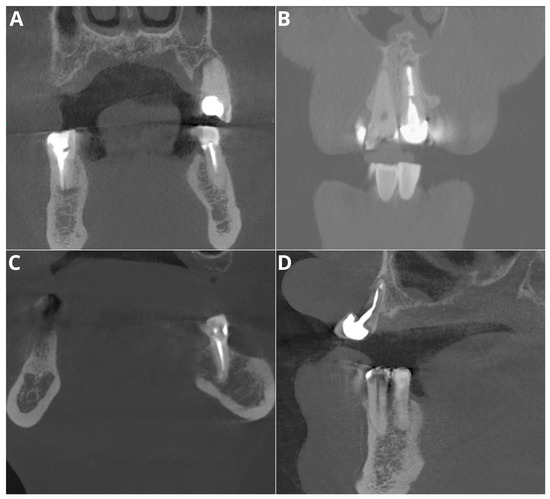

- Probability of filling

- Adequate obturation

- Adequate density

- Overfilling

- Voids in filling

- Short filling

- Probability of filling—evaluation of the presence of radiopaque material within the tooth canals.

- Adequate obturation—assessment of the extent of the filling material up to the apex of the root, verification of material density and consistency through the canal.

- Adequate density—evaluation of the radiopacity and homogeneity of the filling material and identification of areas with lower density indicating voids or inadequate filling.

- Overfilling—examination of any filling material extending beyond the apex of the tooth.

- Voids in filling—identification of radiolucent areas within the filling that indicate the presence of voids.

- Short filling—assessment of the extent of the filling material if it falls short of the tooth apex.